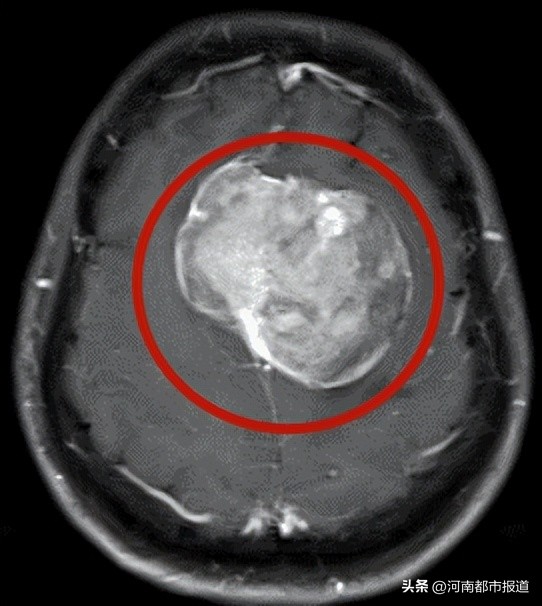

于是,王阿姨到当地医院进行头部CT检查,发现颅内有一块巨大的高密度“石头”。为了弄清楚“石头”的真面目,王阿姨又做了头部磁共振检查。

检查结果显示,王阿姨颅内的“石头”初步诊断为脑膜瘤,直径为7cm,当地医院建议尽早手术。但肿瘤体积较大,后方为中央前回运动区,手术存在一定的风险,运动功能可能会受到影响。

最终,经过神经系统肿瘤MDT多学科会诊,专家一致认为手术是目前唯一的治疗方式,但由于肿瘤质地较硬,体积较大,且肿瘤后方为中央前回运动区(大脑皮层中央前回是大脑的脑回之一,其中存在运动高级中枢),王阿姨的症状就是运动区压迫所致,术中需解除受压并防止运动区损伤,为此,徐欣主任制定了详细的手术方案。